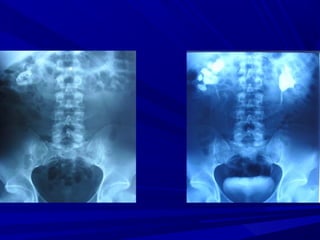

RIÑÓN PÉLVICO